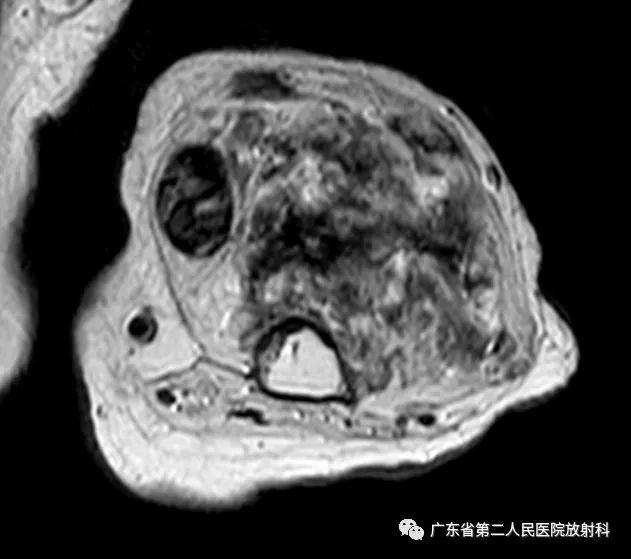

左上肢前壁截肢术后观,左上臂中下段见团块状异常信号,病灶信号明显不均,整体以长T1长T2信号影为主,增强扫描呈明显不均匀强化,末端球形膨大,内见散在少许团絮状短T2长T1且无强化信号。冠状位示病灶整体呈梭形改变,边界欠清,部分包绕肱骨下段,以长T1长T2信号为主,散在少许短T2信号,增强扫描明显不均匀强化,内见散在少许团絮状短T2长T1且无强化信号。肱骨下端边缘欠光整,骨髓未见明确异常信号。